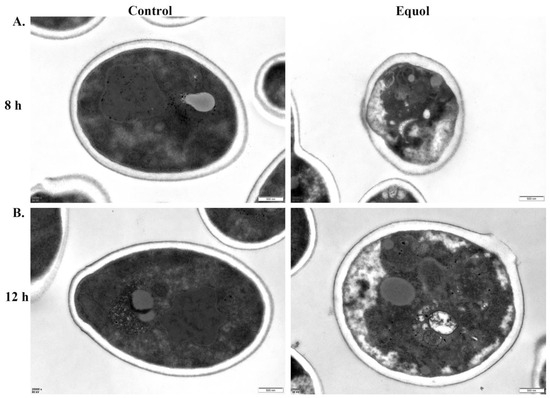

Biological Features, Antimicrobial Susceptibility and Phenotypic Characterization of Candidozyma auris CDC B11903 Grown at Different Temperatures